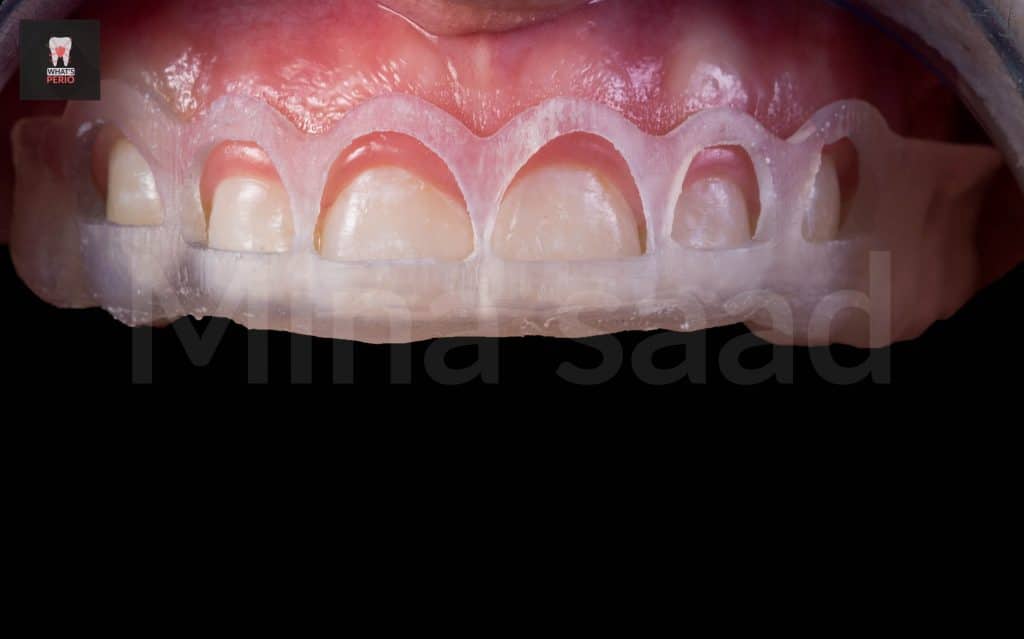

-A 22 years old female come to our clinic seeking a for a solution for her gummy smile .

Clinical examination:

-After excluding other etiologies of gummy smile , it was confirmed that we we have 2 main causes :

1-Hypermobile “hyperactive” lip which is everted more in upper anterior quadrant especially apical to central incisors & lateral incisors.

2-Altered passive eruption. “short clinical crowns”

-Attrition was noted over incisal edges of upper anterior teeth is due to parafunctional habit “bruxism” & it is under control now by a habit breaking appliance “night guard”.